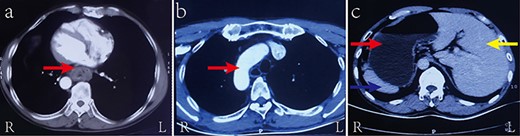

A 55-year-old man was admitted to hospital with progressive dysphagia. The patient was found to have mirror-image dextrocardia (Fig. 1) with an abnormally thickened esophageal wall (thoracic middle-lower segment) observed by way of contrast-enhanced computed tomography (CT) of the chest (Fig. 2a). SIT was observed in the patient, with a right-sided position of the heart and aortic arch (Fig. 2b). Additionally, the spleen and stomach were observed on the right side and the liver on the left by means of CT of the upper abdomen (Fig. 2c). Based on the preoperative examination, the patient was diagnosed with esophageal carcinoma, which was clinically staged as T3N0M0, stage IIA (Union for International Cancer Control esophageal carcinoma pathological stage, 2017). Laparoscopic and thoracoscopic esophagectomy with intrathoracic anastomosis was determined to be the best treatment for the patient’s middle-lower esophageal carcinoma. Throughout the laparoscopy-assisted abdominal surgery, the patient was placed in a supine position. The surgeon stood on the left side of the patient, which is the opposite of the standard position. Under the laparoscope, in accordance with preoperative imaging, the stomach was observed in the right hypochondriac region, the spleen to the right and rear of the stomach, and the liver on

Contrast-enhanced CT of the chest and upper abdomen showing (a) the abnormally thickened esophageal wall of the thoracic middle-lower segment (red arrow); (b) the aortic arch as arranged in SIT (red arrow); and (c) the liver (yellow arrow), stomach (red arrow), and spleen (blue arrow) as arranged in SIT